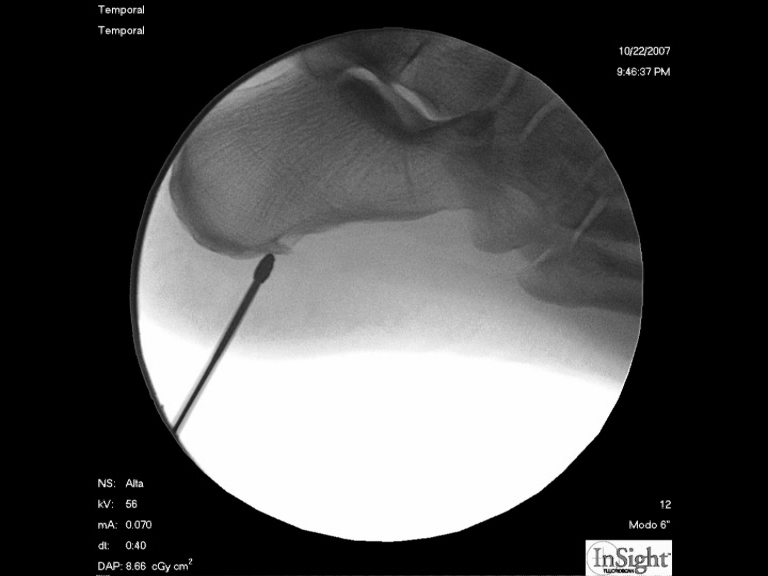

Foto 2

Aquí podemos ver como se introduce el anestésico local en la zona que vamos a intervenir. |